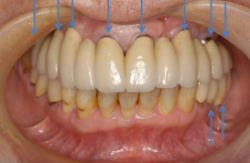

| 症例1 重症の歯周炎に対するインプラント治療(歯を数本失った場合) | ||||||||||||||||||||||||||||||||||

|

| ||||||||||||||||||||||||||||||||||

| 症例2 重度の歯周炎に対するインプラント治療(上の歯をすべて失った場合) | ||||||||||||||||||||||||||||||||||

| 症例3 重症の歯周炎・虫歯と不正咬合に対するインプラント治療 | ||||||||||||||||||||||||||||||||||